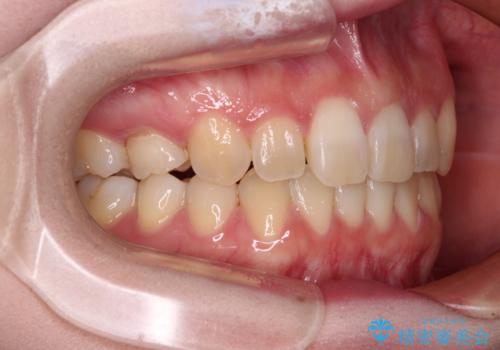

- 前歯のデコボコと強い咬みしめを気にして来院された患者様です。

インビザラインを用いて、前歯の叢生を解消するとともに、ディープバイトを改善していくこととしました。

上顎に乳歯が左右1本ずつ残っていたため、若干咬み合わせに不具合が残りましたが、強い咬合力の原因であったディープバイトをしっかりと改善することができました。